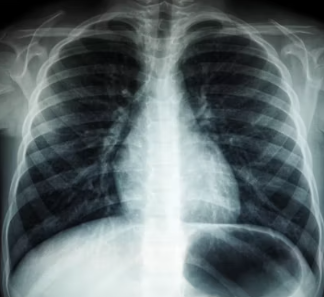

담낭(쓸개) 질환

담낭은 간 아래에 위치하여 담즙을 저장하고 농축하는 기관입니다. 담낭에 문제가 생기면 오른쪽 갈비뼈 아래 통증, 특히 식사 후 통증이 심해지는 경향이 있습니다. 기름진 음식을 먹은 후에 통증이 더 심해진다면 담낭 질환을 의심해 볼 수 있습니다.

담낭염(담낭에 염증이 생기는 것)이나 담석증(담낭에 돌이 생기는 것)이 대표적인 담낭 질환입니다. 통증은 오른쪽 윗배에서 발생하여 등이나 어깨 쪽으로 뻗어나갈 수 있으며, 구토, 소화 불량, 발열 등의 증상이 동반될 수 있습니다.